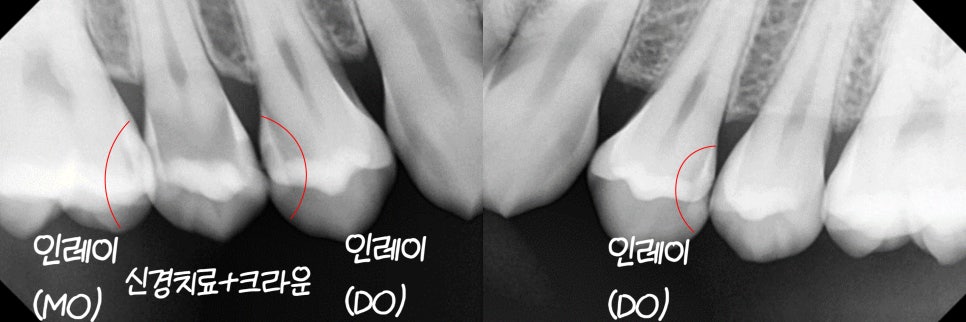

먼저, 육안으로 확인하기 힘든 부위들은

엑스레이 방사선 촬영을 통해 확인합니다.

우식 유무를 좀 더 명확하게 판단하기 위함입니다.

충치가 진행된 부분은

방사선 투과도의 차이가 발생하여

주변보다 어둡게 나타납니다.

이는 방사선이 치아를 통과할 때

밀도에 따라 다르게 흡수되기 때문입니다.

(우식증이 있는 부분은 방서선이 더 많이 통과하기 때문)

어느 치아가 얼마나 썩었는지 알 수 있어

치료 계획을 세우는 데 좋은 지표가 됩니다.